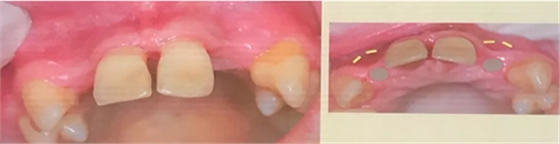

(二) 針對垂直向骨量不足的病例,如下:

該患者的中切牙需要拔除,而雙側(cè)側(cè)切牙的骨寬度和骨高度均不足,應(yīng)該如何處理?由此,教授提出了骨環(huán)植骨技術(shù)。